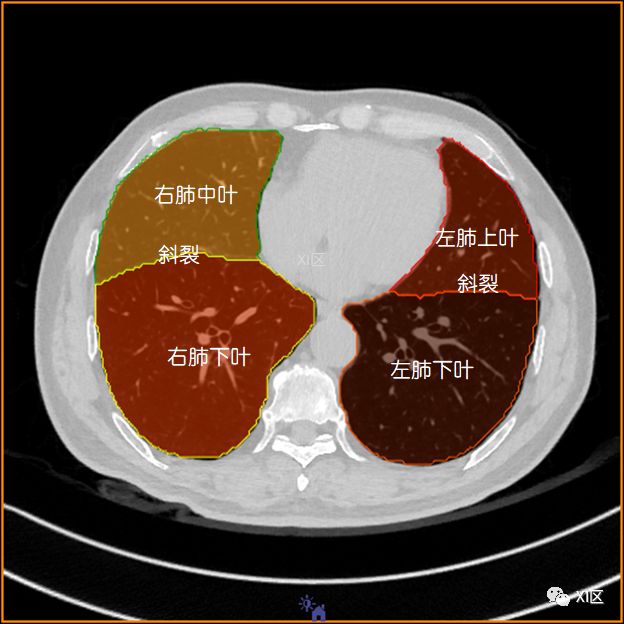

肺的分叶

左肺借斜裂成上、下两叶;右肺借斜裂和水平裂成上、中和下叶三叶。

冠状位